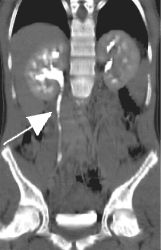

Right image is a curved coronal reconstruction urogram clearly showing partial obstruction with a dilated right ureter and collecting system (arrow) proximal to the stone.